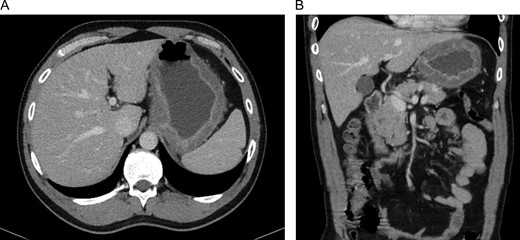

A 45-year-old man presented himself to the emergency department with upper abdominal pain, nausea and vomiting for 3 days. Upon physical examination, the abdomen was tender to palpation but there was no muscle guarding. Laboratory results revealed a high-grade infection, as presented in Table 1. No pneumoperitoneum was seen on the standing chest X-ray. A complementary abdominal CT-scan revealed a widespread thickening of the gastric wall, without signs of perforation (Fig. 1). The patient was admitted and an esophageal-gastro-duodenoscopy revealed diffuse erythema and edema of the gastric wall, suggestive for an acute severe gastritis (Fig. 2). Gastric ischemia or a malignancy, were considered as etiology of the gastritis. H2-blocker and antibiotic therapy with cefuroxime and metronidazole were administered. The next day, the patient deteriorated into a septic shock with multiple organ failure and a high serum lactate (Table 1). A diagnostic laparoscopy was performed. However, due to widespread irreversible gastric ischemia, laparoscopy was converted to a laparotomy (Fig. 3), resulting in a total gastrectomy without primary anastomosis. After surgery the patient was admitted to the intensive care unit for hemodynamic support and continuous veno-venous hemofiltration for multiple organ failure. Because the patient’s condition was considered as unstable, the anastomoses were conducted during a second surgical procedure 2 days after the emergency surgery. During this second surgical procedure a Roux-Y esophagojejunostomy was performed. The overall presentation raised suspicion of streptococcal toxic shock syndrome, causing the multi-organ involvement. This was confirmed when cultures and pathological examination showed a phlegmonous gastritis based on a group A Streptococcus. The patient recovered quickly and 2 weeks after the initial surgery he was discharged.

CT-scan of our patient at admission with widespread thickening of the gastric wall, without signs of perforation in a transversal (A) and coronal (B) coupe.